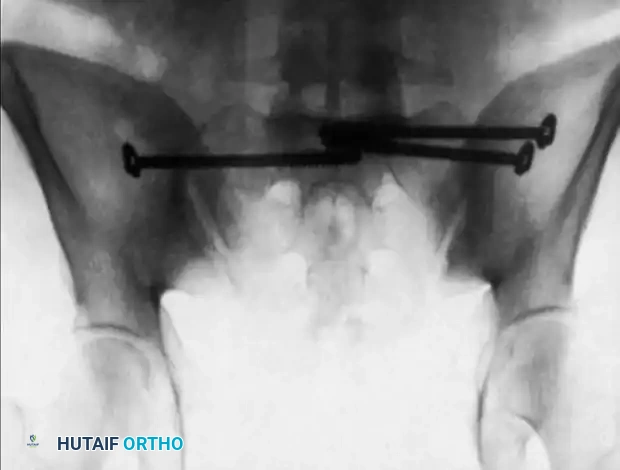

4. Supplemental Fixation and Closure

• If comminution or instability persists, apply a 3.5-mm or 4.5-mm reconstruction plate across the posterior sacrum from ilium to ilium as a tension band, positioned just superior to the greater sciatic notch.